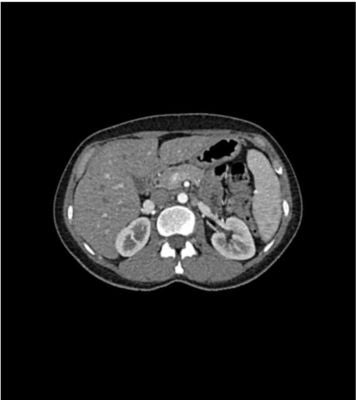

Bones, vessels and soft tissue are displayed authentically with realistic CT values for all tissues at 120 kVp tube voltage in the CT. If the phantom is mainly to be used with other tube voltages (e.g. 100 kVp), the calibration of the CT values can be adjusted accordingly if required. The phantom provides realistic tissue contrasts in X-ray imaging. Air spaces are filled by a material with about -80 Hounsfield units. The phantom provides a highly realistic simulation of a contrast medium enhanced abdomen (late arterial phase) of a patient. The phantom covers the abdomen from the tenth thoracic to the fourth lumbar vertebra. The liver and both kidneys are fully included.